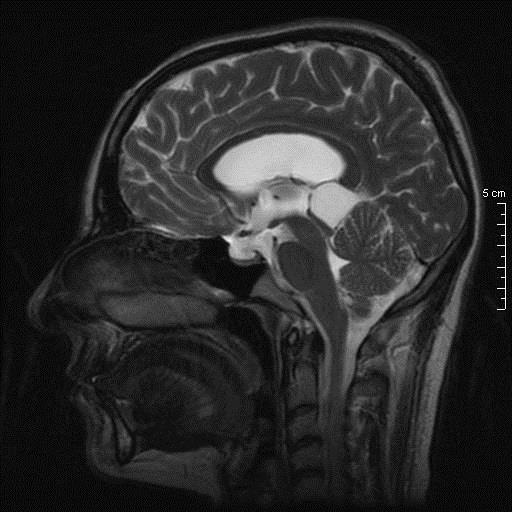

Γυναίκα 34 ετών παρουσιάστηκε με κεφαλαλγία, περιστασιακά διπλωπία και στην εξέταση οίδημα οπτικών θηλών. Η μαγνητική τομογραφία κατέδειξε βλάβη διαμέτρου 26.7 χιλ στην περιοχή της επίφυσης χωρίς ενίσχυση, με πίεση επί του τετραδύμου και σημαντική διάταση του κοιλιακού συστήματος. Σε θέση park bench υποβλήθηκε σε δεξιά πλάγια περιορισμένη ινιακή κρανιοτομία και μέσω της υποσκηνίδιας υπερπαρεγκεφαλιδικής οδού σε ενδοσκοπικά υποβοηθούμενη μακροσκοπικά πλήρη αφαίρεση της βλάβης.

Προεγχειρητικός απεικονιστικός έλεγχος